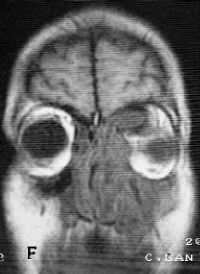

Sinusitis fúngica alérgica: aspectos clinipatológicos y hallazgos en TC y RM.

Allergic fungal sinusitis: clinico-pathological aspects. Findings on CT and MR